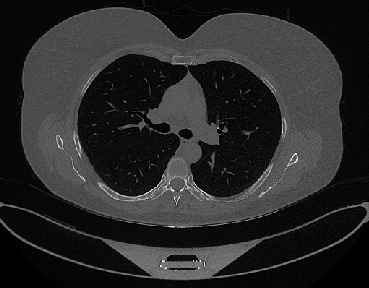

Figure 1 shows four CT scan slices, two from a non-COVID-19 CT scan, on the left and two from a COVID-19 scan, on the right. Bilateral ground glass regions are seen especially in lower lung lobes in the COVID-19 slices.